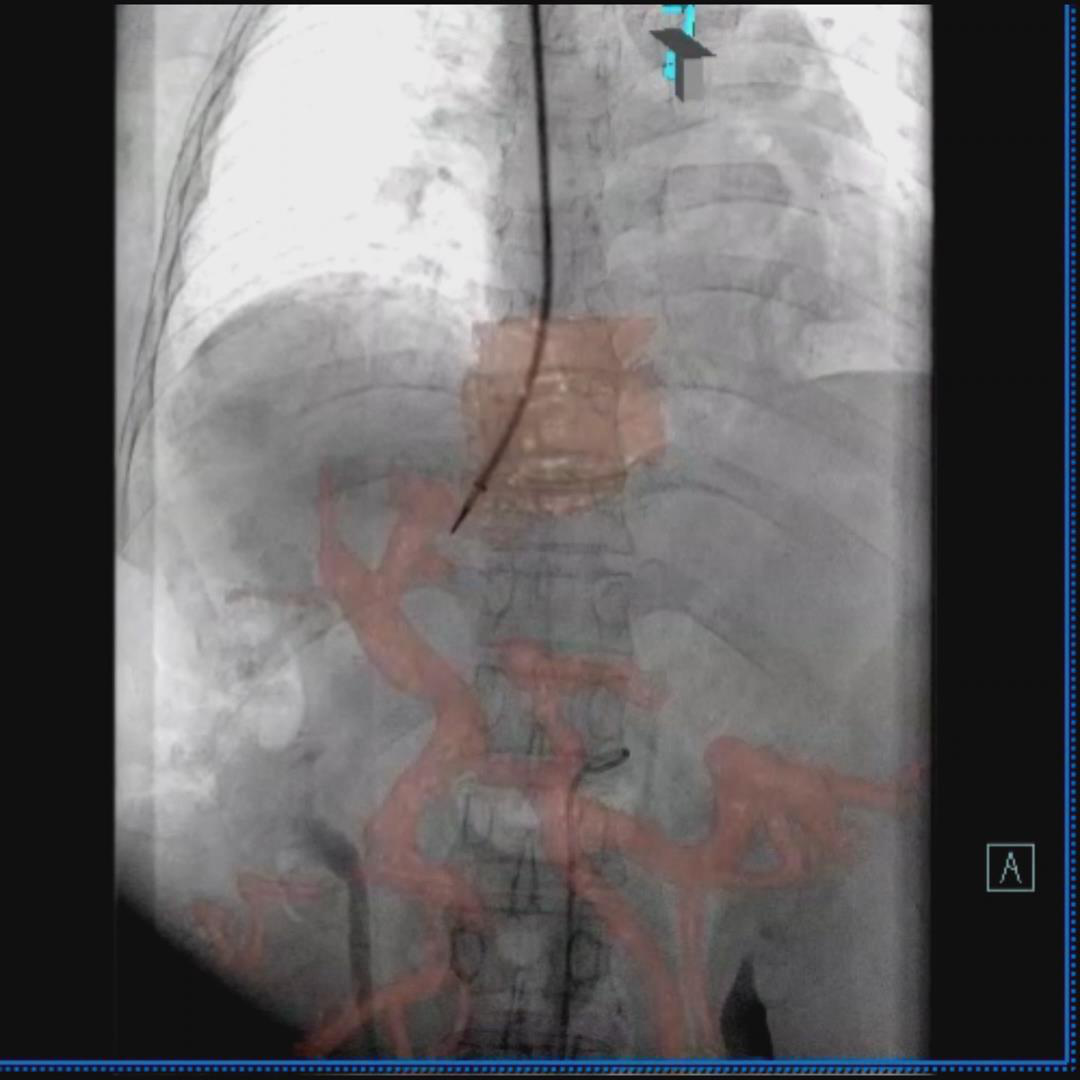

术中3D融合影像引导门静脉穿刺